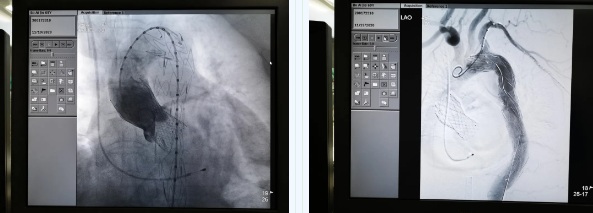

張金洲副院長關注著手術的每一個細節(jié),從建立軌道、跨瓣、釋放瓣膜、支架定位、造影和食道超聲確認,每一步都緊張而有序地進行著。為了最大程度保障病人安全,心臟外科程亮副主任也帶隊建立動靜脈入路,以備緊急體外循環(huán)。經(jīng)過團隊每一位成員的密切配合,在近四小時的緊張奮戰(zhàn)之后,“TAVR TEVAR”復合手術順利完成;經(jīng)過造影和食道超聲證實:人工主動脈瓣無返流無瓣周漏、冠脈顯影良好,主動脈覆膜支架無內(nèi)漏無移位。